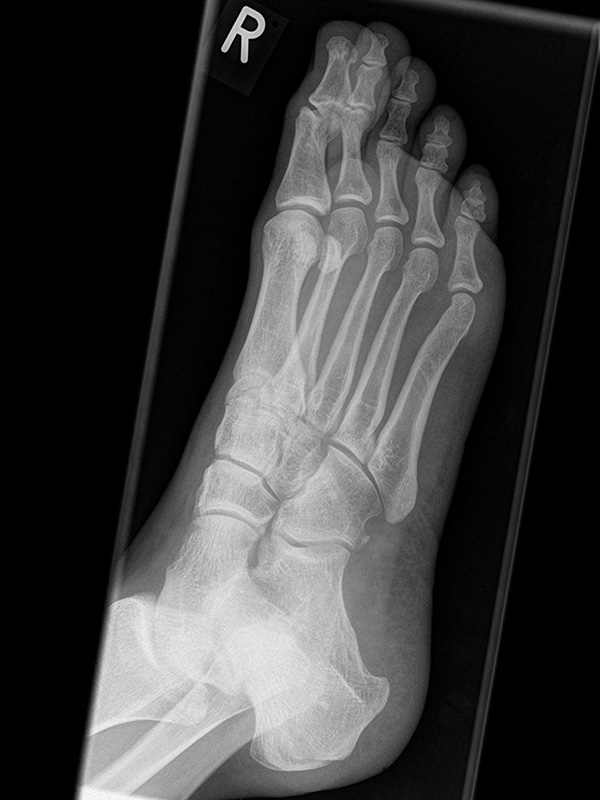

Fuß dp (dorsoplantar) mit Belastung

Positionierung:

• Der Patient steht unter gleichmäßiger Gewichtsbelastung auf beiden Füßen.

• Die Fußachse ist nach vorne gerichtet.

• Die Kassette liegt unter dem zu röntgenden Fuß.

• Der Zentralstrahl wird auf das Tarsometatarsalgelenk II zentriert.

• Die Röntgenröhre ist 15° vertikal gekippt.

• Anmerkung: Technisch lässt sich die Röhre beim stehenden Patienten nicht in 0° über dem Fuß positionieren. Eine Kippung der Röhre um 15° erlaubt darüber hinaus eine bessere Einsicht in die tarsometatarsalen Gelenke.

Kennzeichen des Röntgenbildes:

• Standardabbildung des Fußes zusammen mit der belasteten seitlichen Aufnahme und der unbelasteten Schrägaufnahme.

• Die belasteten Aufnahmen liefern relevante Informationen zur Fußstatik und sind die Grundlage aller achskorrigierenden Eingriffe an Vor- und Rückfuß.

• Sämtliche Winkelbestimmungen beziehen sich auf belastete Aufnahmen.

Besondere Bemerkungen zum Beispielbild:

• Schwere Hallux valgus Deformität.

• Die Sesambeine sind luxiert, ebenso das Großzehengrundgelenk. Luxation des Metatarsophalangealgelenks II.

• Degenerative Veränderungen der tarsometatarsalen (TMT) Gelenkreihe, betont TMT II und III.

Zur Vollansicht und zum Lesen der Bildbeschreibung bitte die Bilder anklicken.